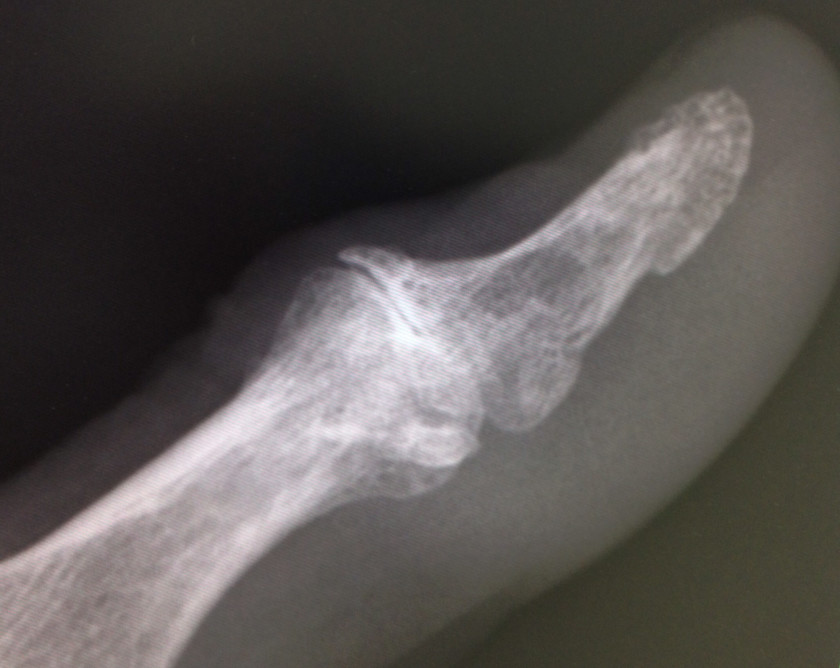

2017/04/17 バネ指の正体

母指が「ポキン、ポキン」とするからと本人ばかりか、内科医の主治医も『弾撥指(バネ指)』

と診断していた症例。関節の変形、及び再現性のある、一定した関節可動域制限から変形性関節症と診断。レントゲン写真にて確定。主治医は腱鞘切開術の依頼をする予定だったとか・・・。

ムダなキズをつくらずに済みました。

母指が「ポキン、ポキン」とするからと本人ばかりか、内科医の主治医も『弾撥指(バネ指)』と診断していた症例。関節の変形、及び再現性のある、一定した関節可動域制限から変形性関節症と診断。レントゲン写真にて確定。主治医は腱鞘切開術の依頼をする予定だったとか・・・。